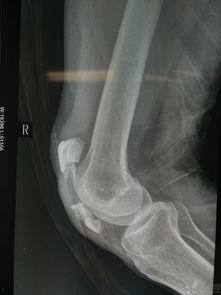

想象当你的骨头因为骨折而断裂时,医生会用克氏针将断裂的骨头固定在一起,让它们慢慢愈合。这个过程听起来是不是有点神奇?其实,这就是克氏针的魔力所在。

2. 手术过程:手术过程中,医生会在患者的骨折部位打一个小孔,然后将克氏针从孔中穿入,穿过骨折的骨头,最后固定在皮肤外。这个过程听起来有点复杂,但医生们却游刃有余。